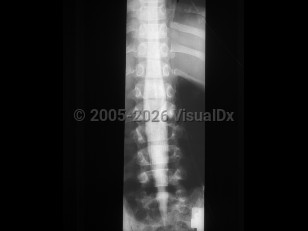

Diastematomyelia in Adult

Diastematomyelia, split-cord malformation (SCM), is a rare congenital abnormality in which there is partial or complete cleft in the spinal cord by a sagittal osseous or fibrous septum. It is seen predominantly in females, most often affecting the lower thoracic or upper lumbar segments. Clinically, diastematomyelia often presents as tethered cord syndrome (back pain, abnormal gait, spasticity, bowel / bladder incontinence) in children or young adults, although symptom onset may occur at any age. Patients may have a midline cutaneous abnormality such as a hairy patch or dimple over the affected area. There are two classifications:

• SCM type 1 consists of two hemicords, each with its own dural sheath, separated by a bony or cartilaginous septum.

• SCM type 2 consists of two hemicords within the same dural sheath but separated by a fibrous septum.